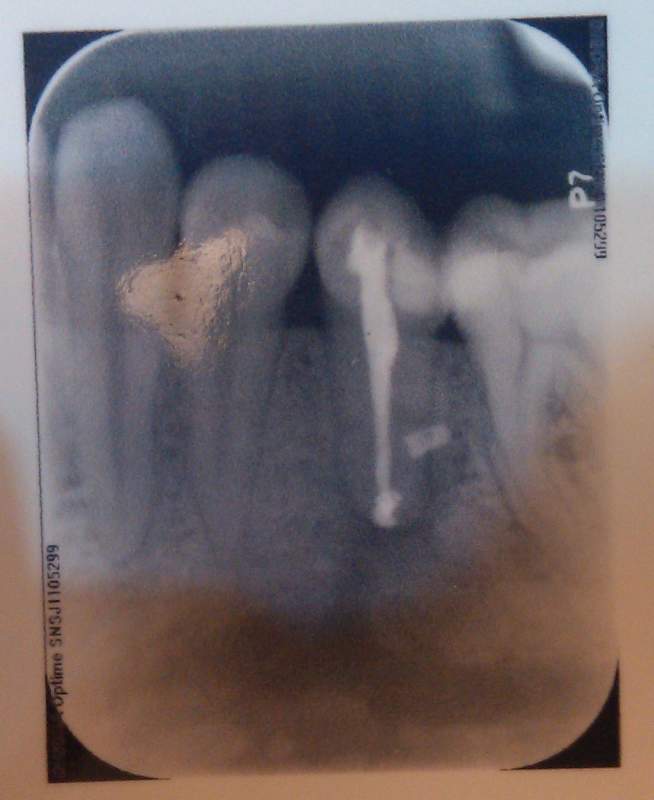

Çë½Ì¸÷λ´óÉñ£¬¹ØÓÚ¸ù¼âÄÒÖ׸ù¹ÜÖÎÁƺóµÄÑÀƬ ÒÑÓÐ2È˲ÎÓë